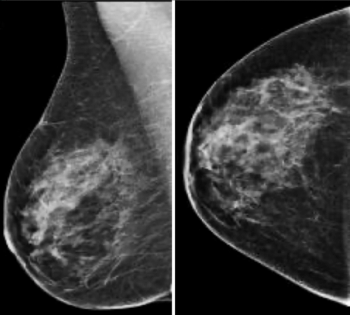

The improved cancer detection rate that catches more cancers with favorable prognoses and the lower false negative rates, improves patient outcomes and puts DBT on track to replace 2D mammography as the gold standard for screening.

Hologic’s Jennifer Meade, division president of breast and skeletal care, discusses the focus for breast imaging in the near future and some latest technologies.

Implementing artificial intelligence tools with breast imaging can pinpoint overlooked interval cancers and decrease provider workload in screening mammography programs.